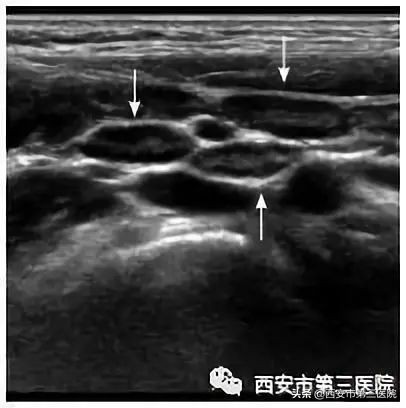

超声检查对于各种原因导致的小儿腹痛有很大的鉴别作用,小孩子腹痛最常做的辅助检查是超声检查,而且因为其简单、快捷而成为越来越常规的检查。肠系膜淋巴结炎超声检查会很直观的在小儿腹腔内探及明显异常的淋巴结声像图,这对于临床诊断有很大的帮助。